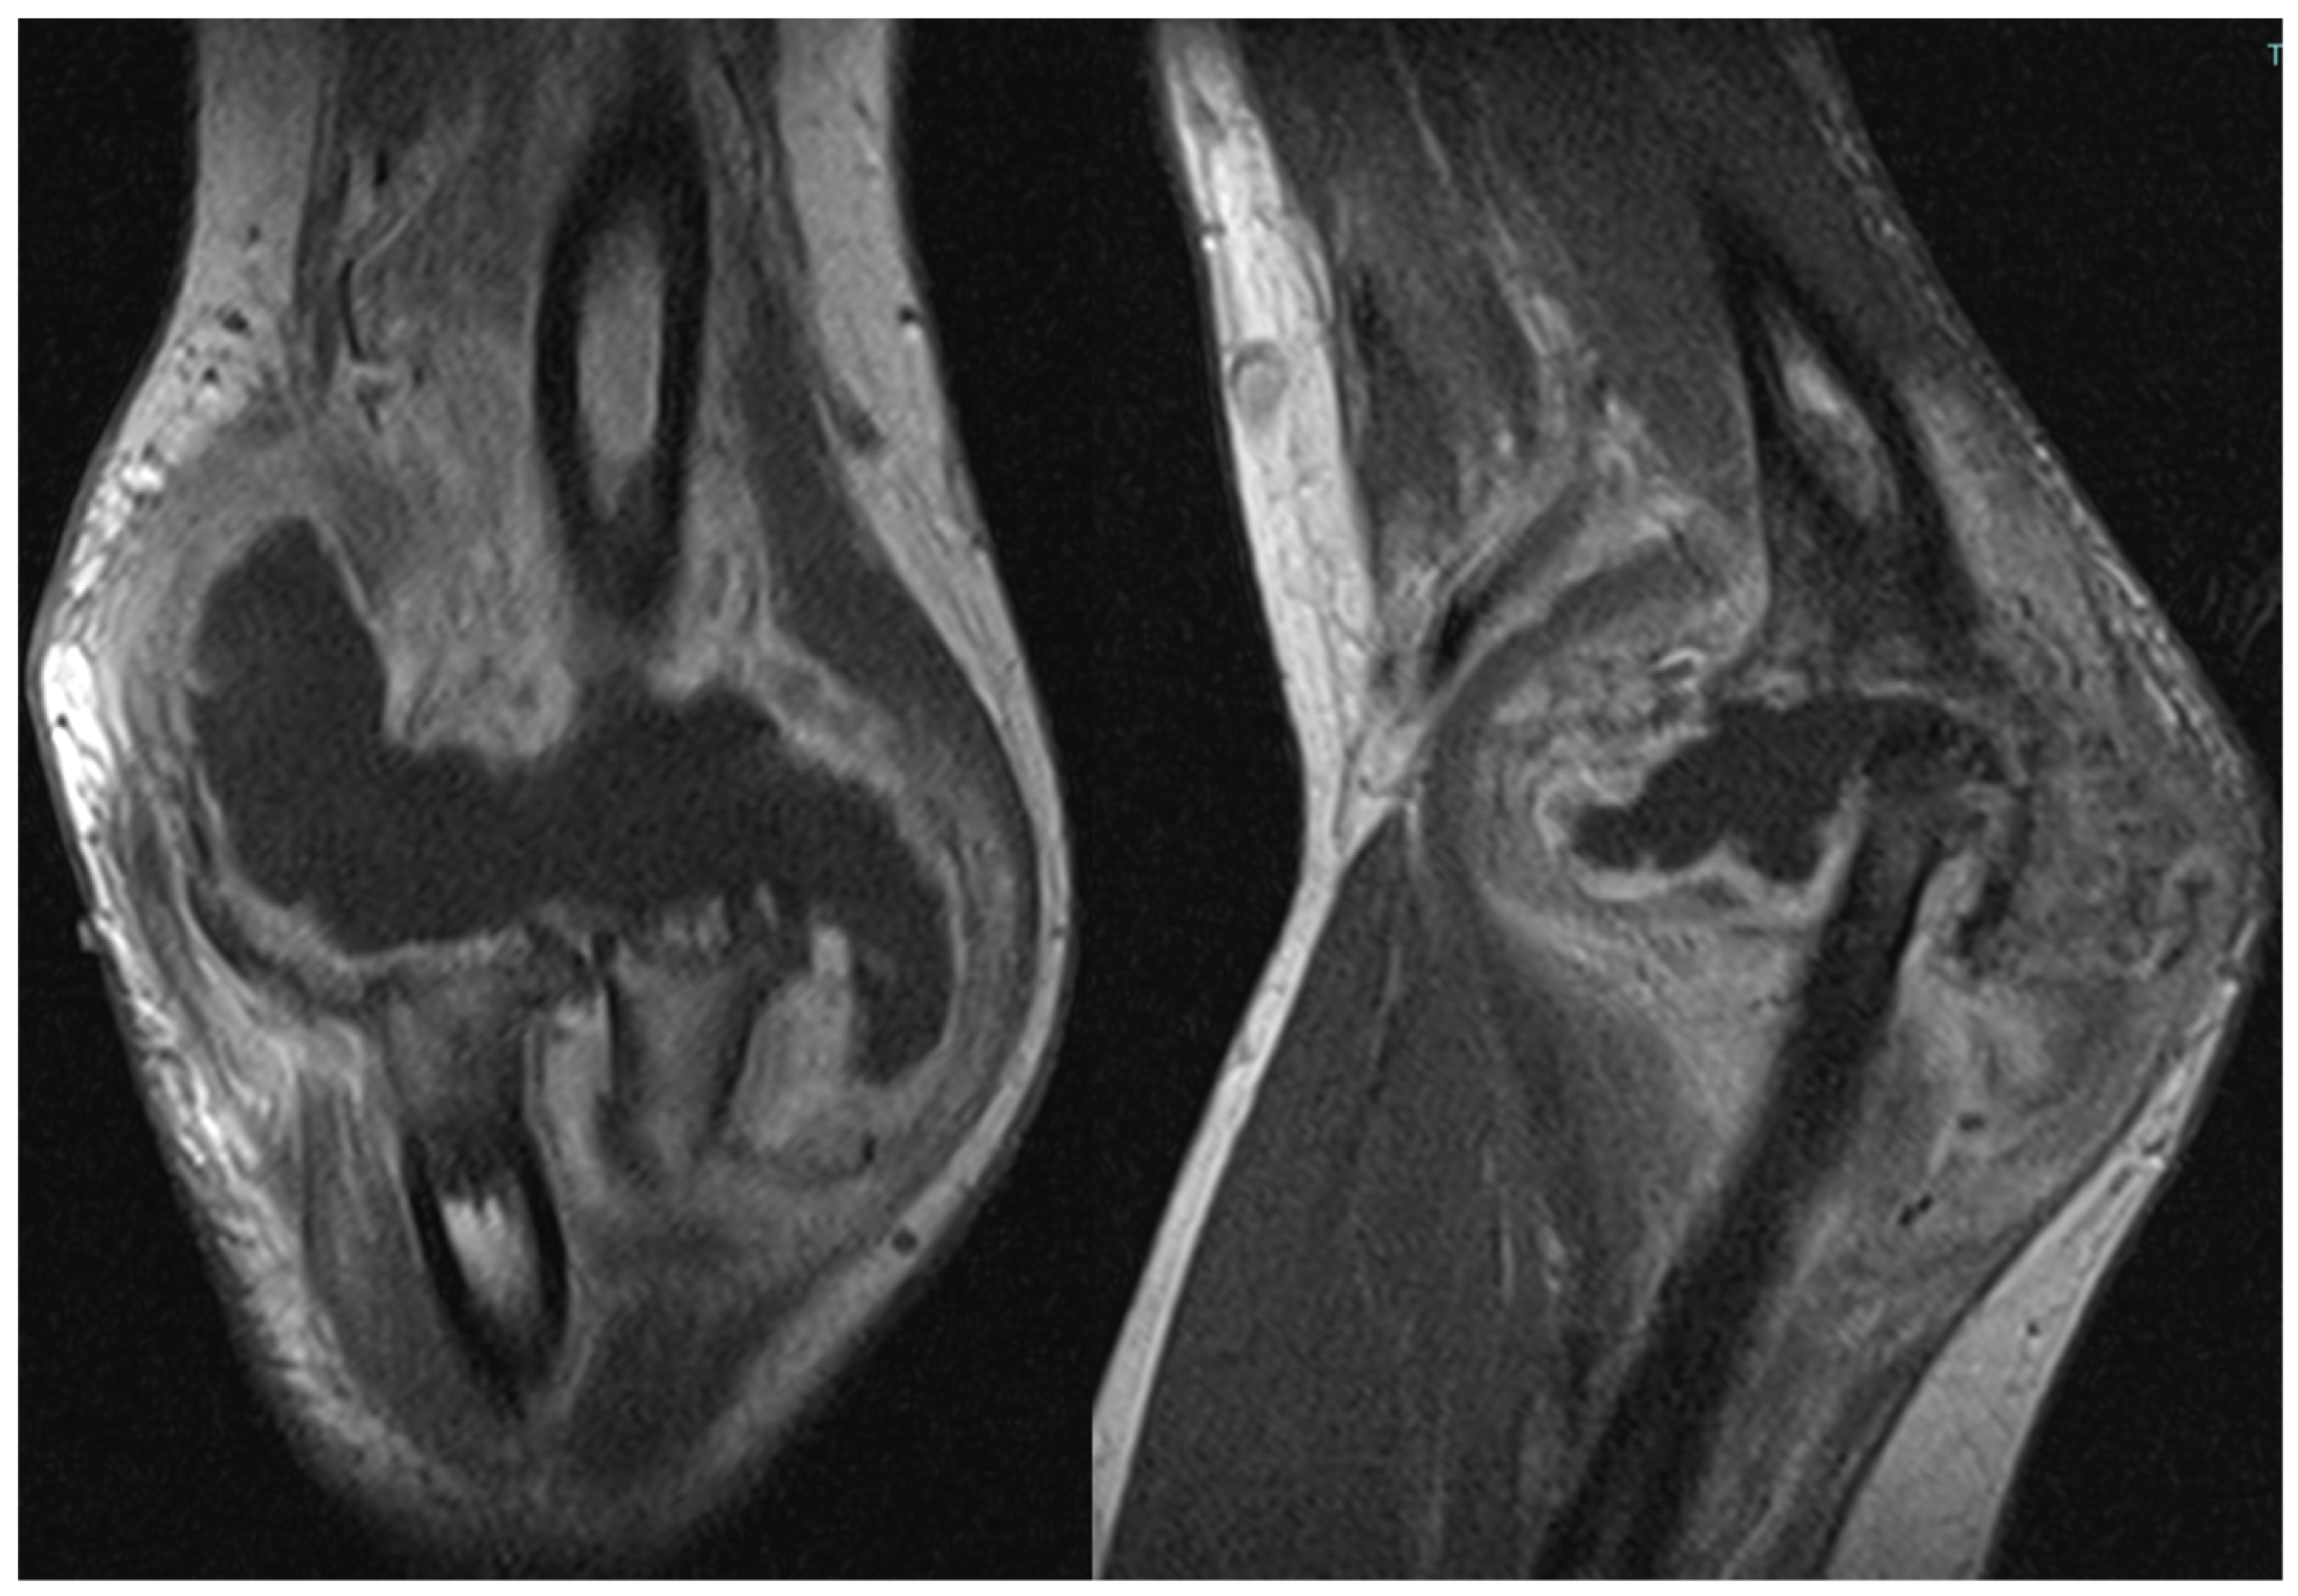

The patient also underwent magnetic resonance imaging (MRI) with and without contrast medium, which revealed a subluxation between the articular surfaces of the elbow joint and contrast enhancement and edema in the spongy bone of the distal third of the humerus and the proximal third of the radius. Additionally, there was a periosteal reaction in the humeral site without identifiable bone lesions on the imaging. An abundant layer of joint effusion with blood clots and loose bodies was evident at the joint level. The synovium appeared thickened and full of contrast enhancement, and periarticular soft tissues also appeared thickened with edema and soft contrasting infiltration in the proximal ulnar side. In the context of the known basic arthropathy and the clinical presentation, these findings based on radiological evidence suggested more for an arthritic arthro-synovitis picture with soft tissue involvement, without excluding the infectious nature, than osteomyelitis because despite the bone subversion there weren’t cavity of necrotic bone with fistula and bone marrow inflammation (Figure 2).

Figure 2. Magnetic resonance imaging (MRI) coronal and sagittal T1 weight views of the right elbow. Involvement of the periarticular soft tissue.